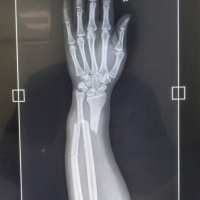

你这个骨折有点严重哦!图上看确实存在视觉盲区和容易产生错觉,对骑车的人不太友好

该安全岛路沿台阶无反光油漆、夜间反光立柱损坏并长期缺失无监管维修、岛上未设置指示牌、长度设计极其不合理。

你这骨折有点恐怖。我们的市政建设不应该仅仅考虑好看,更要考虑人性化----------